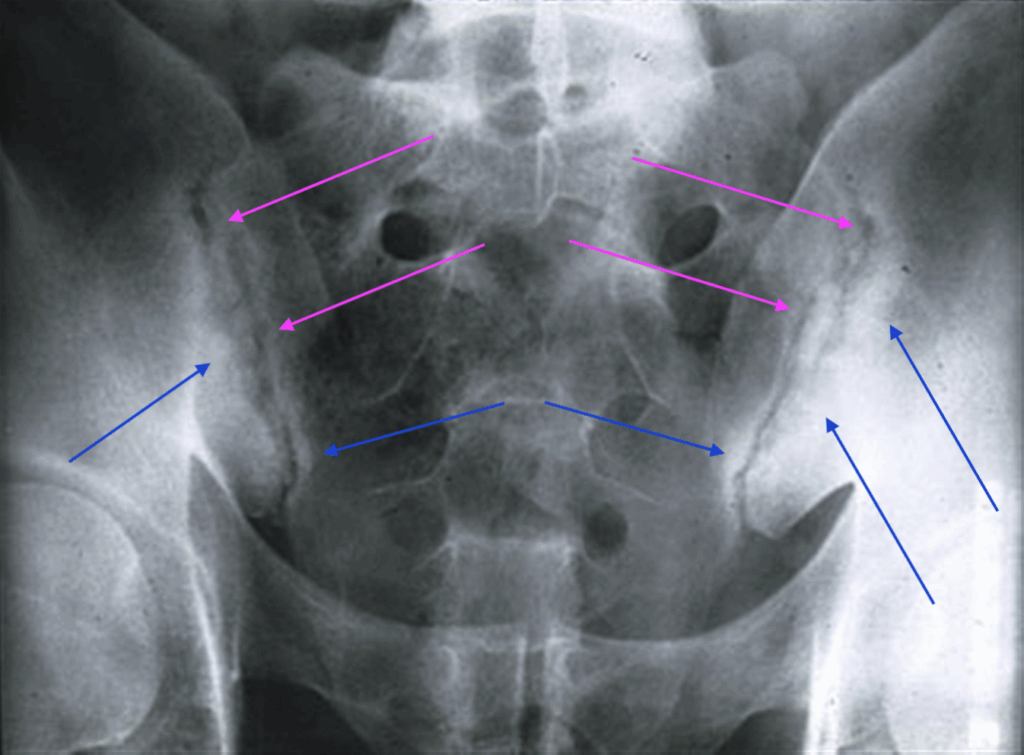

Here’s the key X-ray image:

The MAGENTA arrows show bone condensation and the BLUE arrows show increased joint irregularity – common findings in AS

The combination of History, Age, Gender, Symptoms, Orthopaedic Tests, Blood Test results and Radiographic results confirmed the diagnosis of early stage Ankylosing Spondylitis.